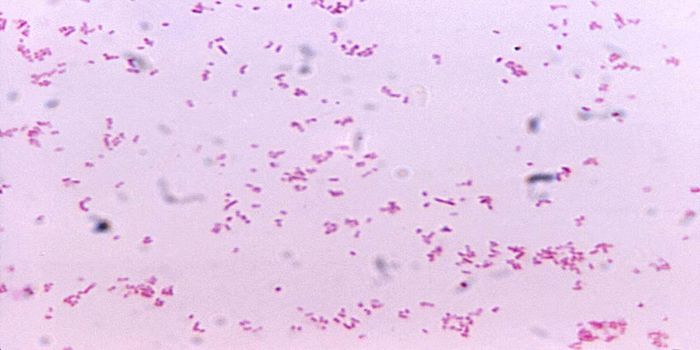

FEB 23, 2019Health & MedicineFacklamia species are Gram-positive, facultatively anaerobic bacteria that present a challenge for clinical labs to ...